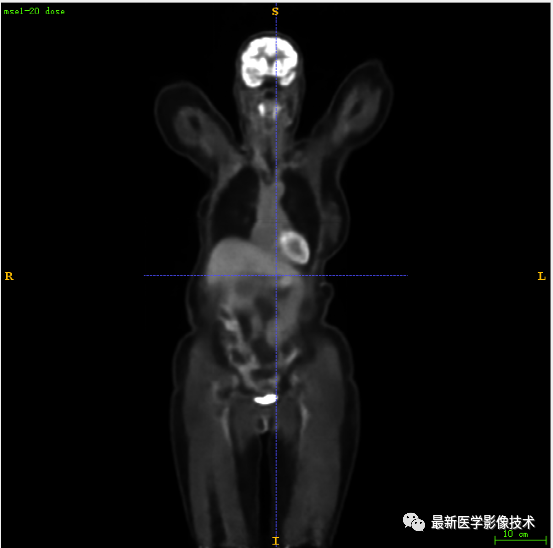

7.3、低剂量10重建结果

第一张是低剂量10的PET图像,第二张是full剂量PET图像,第三张是网络重建的PET图像。